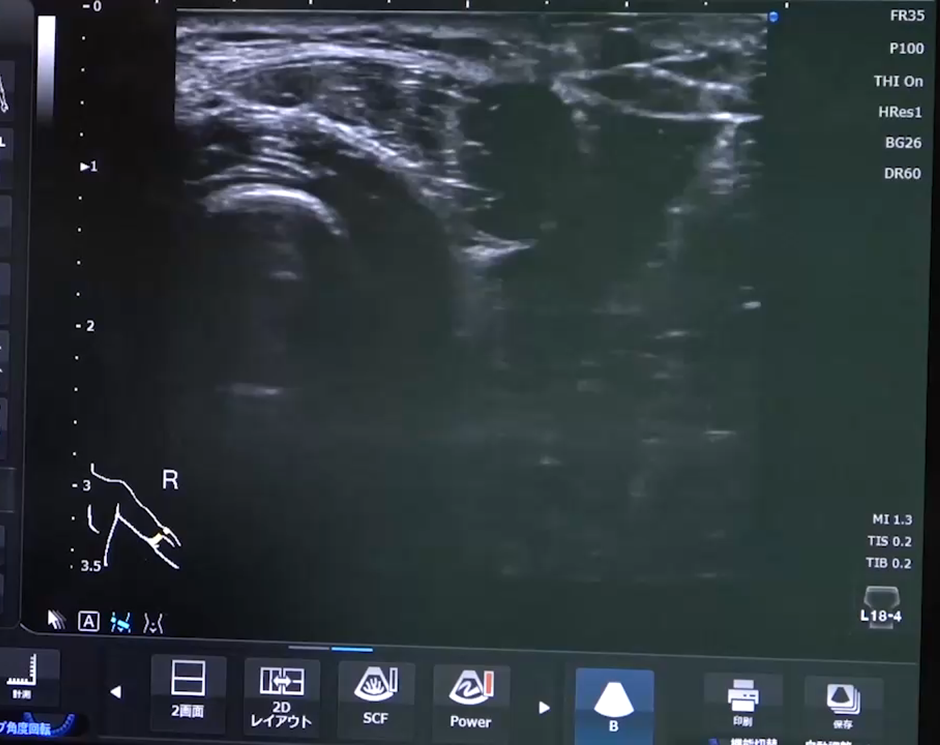

筋膜リリース、筋膜性疼痛とは筋膜性疼痛(筋筋膜性疼痛症候群)とは?筋膜リリースと筋膜ハイドロリリースを“過不足なく”理解する筋膜リリース、筋膜性疼痛とは

1. 筋膜性疼痛(筋筋膜性疼痛症候群:MPS)って何? 「レントゲンやMRIで“異常なし”と言われたのに、首・肩・腰がずっと痛い」そんなときに候補に上がる代表格が 筋筋膜性疼痛症候群(MPS) です。 日本のペインクリニック領域の治療指針では、MPSを「過敏...